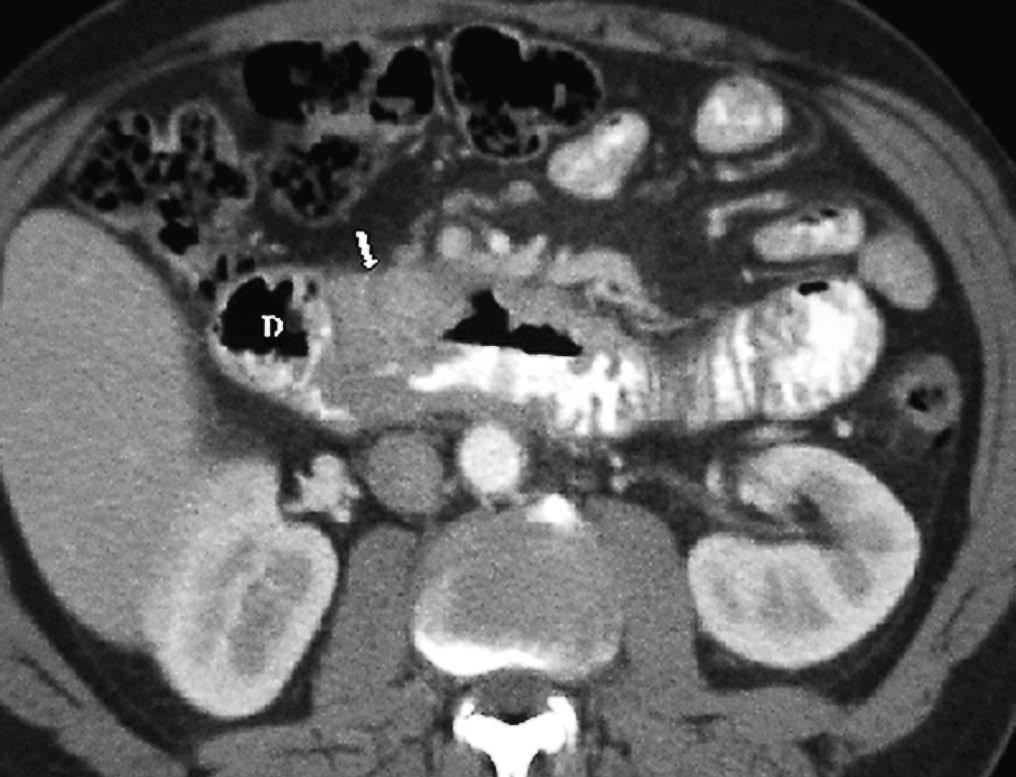

El duodeno es una localización infrecuente de diverticulitis. La imagen radiológica consiste en un engrosamiento de la pared del duodeno asociado a un divertículo, en ocasiones con un enterolito en su interior, con inflamación de la grasa adyacente16 (fig. 9).

Fig. 9--Diverticulitis duodenal. (A) En la ecografía se observa un divertículo (flechas) con engrosamiento de pared duodenal (D) y alteración de la grasa adyacente (*). (B) Tomografía computarizada de otro paciente con inflamación de divertículo duodenal. Se oberva una lesión quística (punta de flecha) de pared gruesa y borrosa, con material en su interior. P: Páncreas.